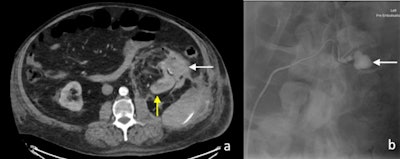

(A) Arterial phase CT image of perinephric hematoma (white arrow) at the site of partial nephrectomy. The residual left kidney is indicated by the yellow arrow. (B) Active extravasation of contrast (white arrow) was confirmed on digital subtraction angiography. All figures courtesy of Dr. Jean S.Z. Lee and colleagues and Insights into Imaging.

(A) Arterial phase CT image of perinephric hematoma (white arrow) at the site of partial nephrectomy. The residual left kidney is indicated by the yellow arrow. (B) Active extravasation of contrast (white arrow) was confirmed on digital subtraction angiography. All figures courtesy of Dr. Jean S.Z. Lee and colleagues and Insights into Imaging.Open and laparoscopic radical nephrectomy is the gold standard in the management of large renal masses. For smaller lesions, nephron-sparing procedures such as partial nephrectomy or percutaneous therapies are increasingly favored.

"Early CT is indicated to assess the clinically suspected complications of surgery and to enable early management," stated Lee and colleagues. "Two main complications following nephrectomy requiring CT is hemorrhage and urinary leakage. Postoperative hemorrhage may arise from an unsecured artery, or days to weeks later due to the rupture of a pseudoaneurysm of an intrarenal artery."

The presence of a postoperative perinephric hematoma can be demonstrated by CT, ultrasound, or MRI, but the site of active hemorrhage is best demonstrated on a CT angiography or digital subtraction angiography (DSA).